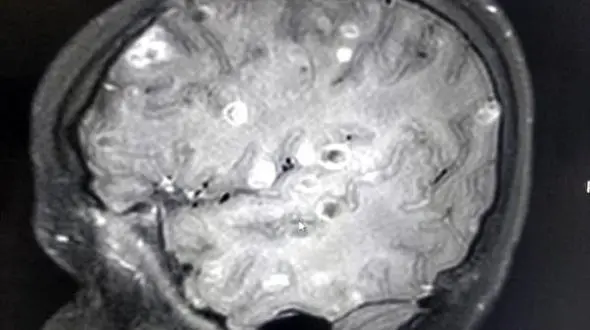

رکنا: دختر بچه 8 ساله بعد از خوردن میوه های نشسته اتفاقی عجیب برایش افتاد و در مغزش مشکلات عجیبی پیش آمد.